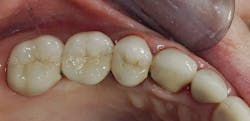

My suggestions are based on the dental literature and my many years of practice experience. Consider the factors below to help you decide whether pins or posts are needed. Figures 1–3 show the need for the restorative buildup procedures.